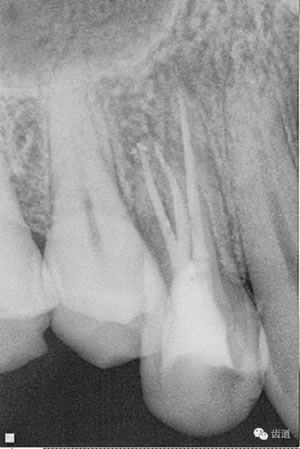

處理:放置橡皮障,去除暫封,超聲結(jié)合2%CHX清除遠(yuǎn)頰根管內(nèi)氫氧化鈣糊劑,主牙膠試合后95%酒精沖洗干燥根管,結(jié)合AH Plus糊劑連續(xù)波熱牙膠垂直加壓充填根管,樹脂分層粘接修復(fù)牙體。建議定時復(fù)診進(jìn)行嵌體修復(fù),患者未執(zhí)行。